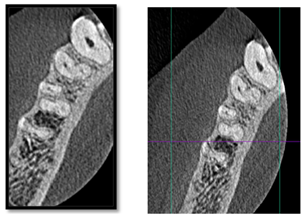

A 35‑year‑old female patient walked into our clinic with the chief complaint of severe pain in the lower jaw right posterior region since 2 days. Oral examination revealed occlusal caries in the lower right mandibular first premolar and secondary caries in second premolar. The tooth was sensitive to percussion and showed an exaggerated response on cold and electric pulp testing. Radiological findings showed coronal radiolucency involving pulp, widening of periodontal ligament (PDL) space, large pulp chamber without any constriction at cementoenamel junction, the condition was diagnosed as acute irreversible pulpitis with apical periodontitis in both the premolars (Figure 1) Cone-beam computed tomography (CBCT) was carried out for confirming numbers of roots and canals of mandibular right second premolar. The CBCT images were taken out using three‑dimensional (3D) Accuitomo scanner (J. Morita, Kyoto, Japan), with Viewer Plus software (J. Morita), which produced a smallest field of view images, to reduce the radiation dosage. A three canals were found, two buccally and one lingually (Figure 2). A non‑surgical root canal treatment was planned accordingly. The patient received local anesthesia with 2% lidocaine and 1:100,000 epinephrine and the rubber dam placement. Following the removal of old filling, careful examination of the pulpal floor revealed three separate mesiobuccal, distobuccal and lingual orifices. The access cavity outline was modified into triangular shape to establish straight‑line access for all root canals. The working length was established using Root ZX II (J. Morita, Tokyo, Japan) and confirmed radiographically (Figure 3). Instrumentation is achieved with Hero Shaper (Micro Mega) to size 30 4%, copious irrigation with 2.5% NaOCl and 17% EDTA was carried out during the instrumentation phase. All canals were dried with sterile paper points and then filling using matching gutta‑percha cones and AH‑plus sealer (Dentsply Maillefer, Ballaigues, Switzerland) until canal orifices (Figure 4) Postendodontic restoration was done followed by tooth preparation and Zirconia‑based full coverage crown cementation. Fifteen months follow‑up radiograph revealed satisfactory healing and healthy status of periapical tissues (Figure 5).

Figure 2 The axial plane of CBCT of #45 showing three canals. (Apical & middle Section).